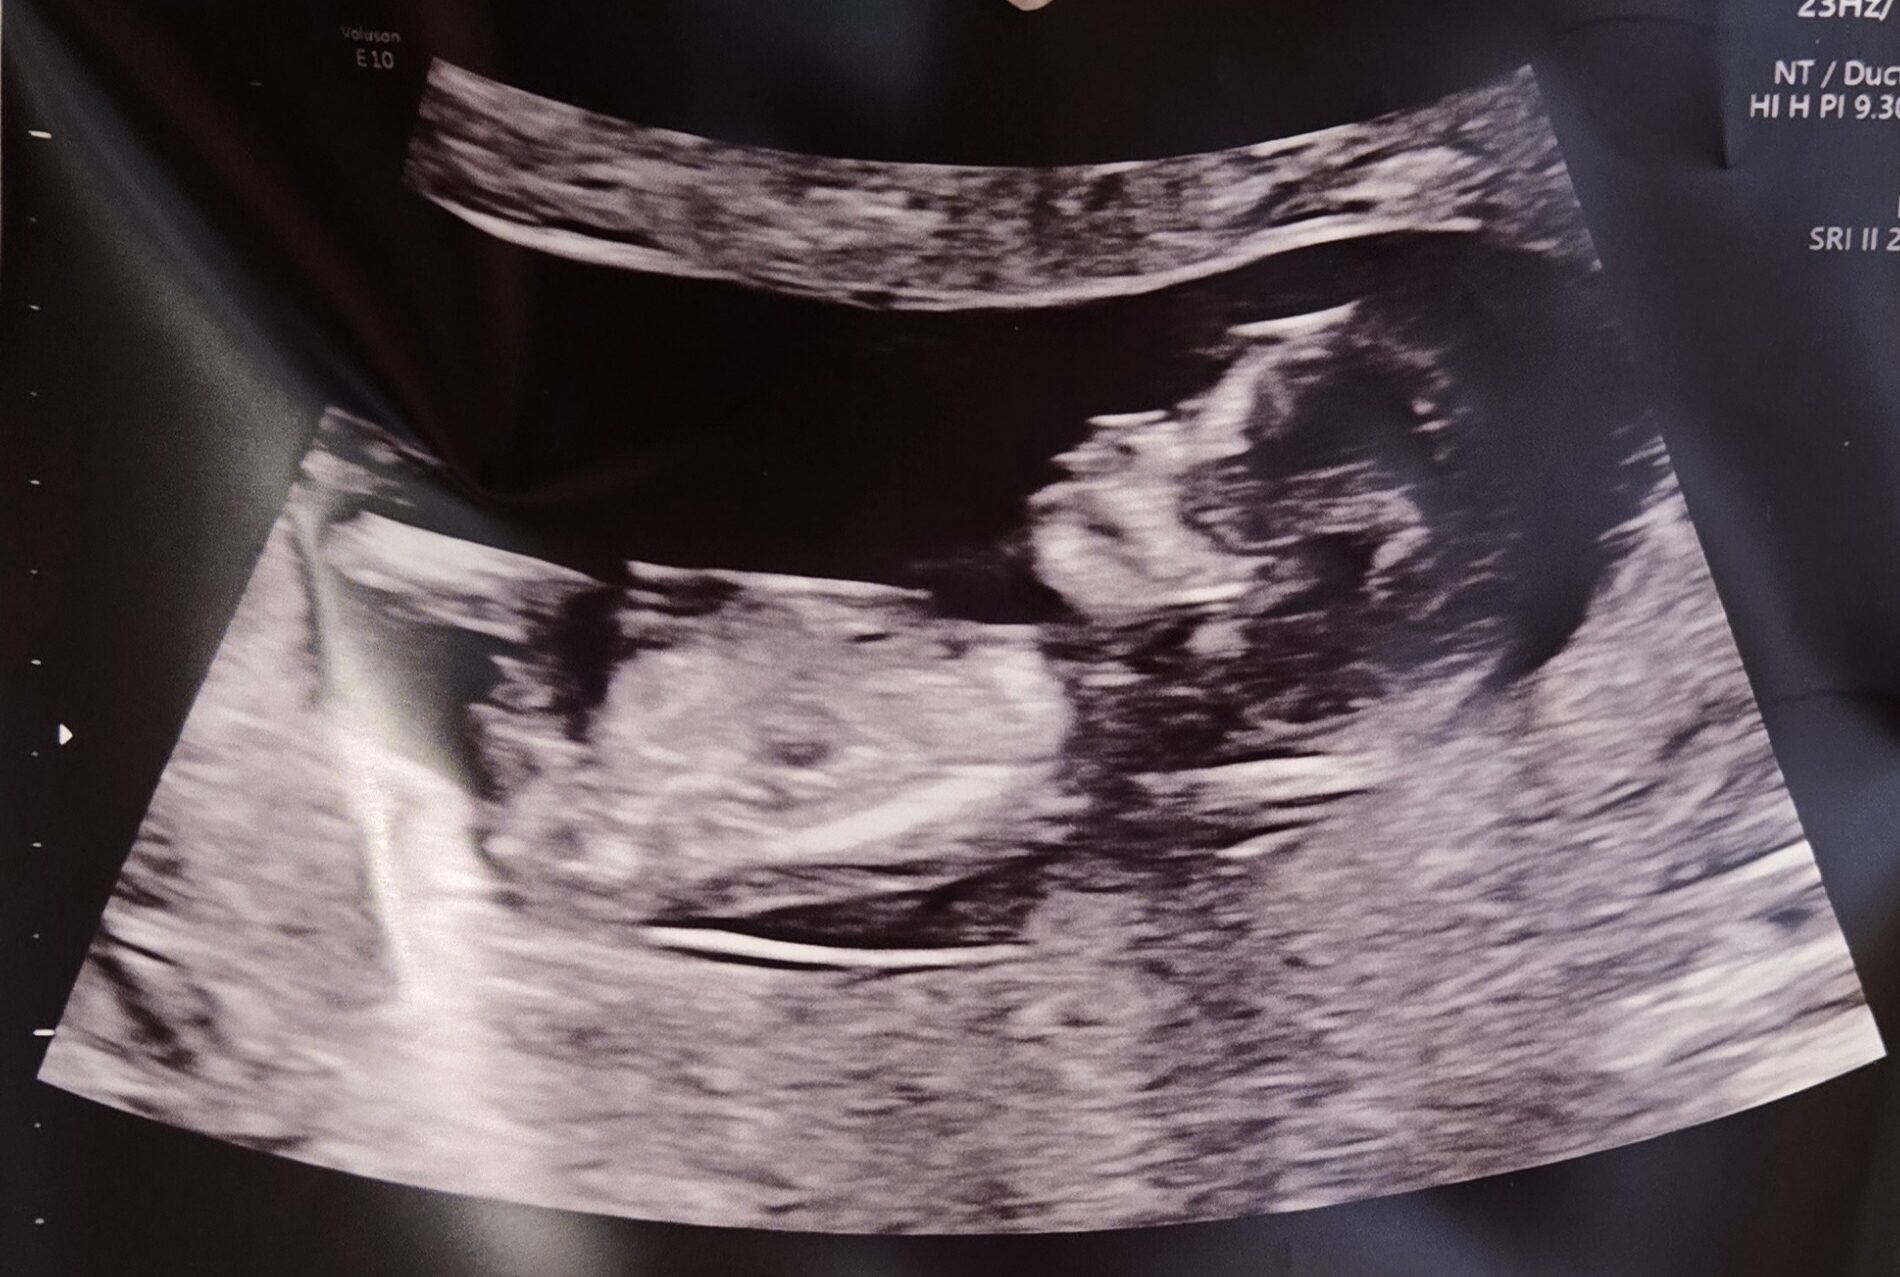

Patient age: 37

Tubal ligation type: Resection (tied or cut)

Patient hometown: Providence, Rhode Island